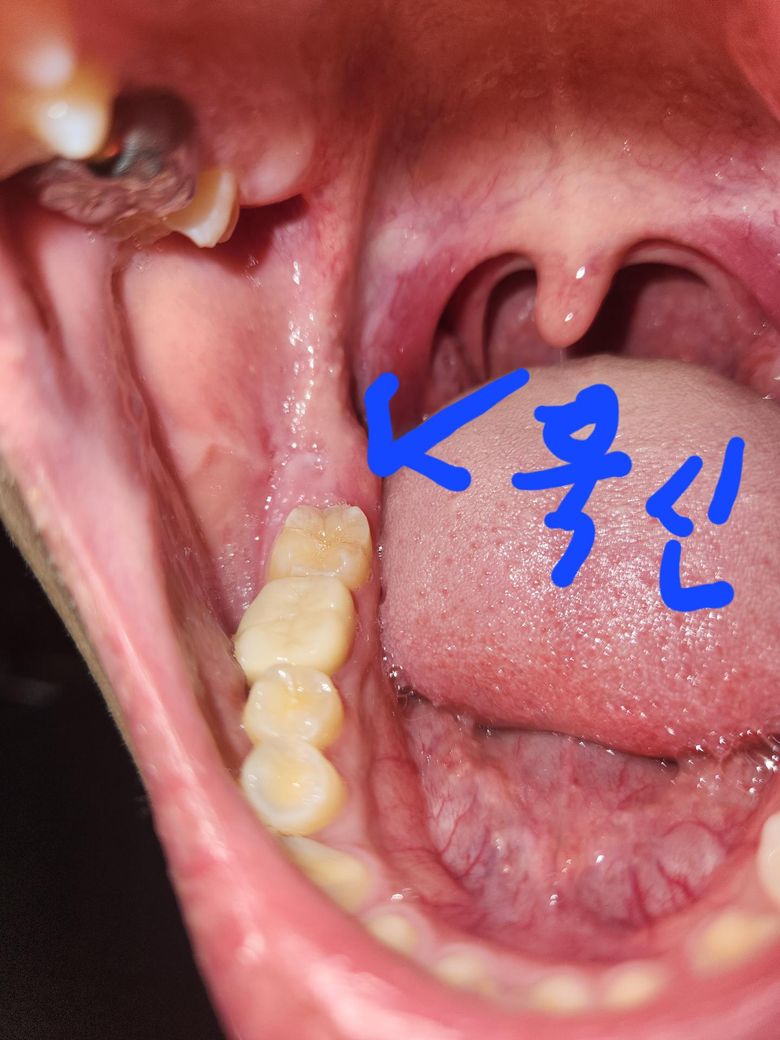

이거 사랑니인가요? 나이는 17살입니다.

한쪽 어금니 뒤에 잇몸은 씹을 때 욱신거리고 다른 한쪽은 잇몸 살이 약간 갈라졌습니다.

증상이 생긴 지는 3일 정도 됐어요.

• 1번 째 사진

사진으로 보이는 부위는 사랑니가 올라오는 부위가 맞습니다. 사랑니는 똑바로 맹출되었을 경우 그냥 사용해도 되지만 사랑니로 인해서 불편감이 있다면 발치를 하는것이 좋을수 있습니다.

해당 치아부위는 하악 사랑니가 원인 일 확률이 매우 높습니다 하지만 치과 파노 라마 사진 촬영 후 확진이 필요합니다 사랑니는 정상적으로 올바르게 이가 나고 치아 관리를 매우 잘 할 자신이 있으면 비발치 해도 되지만 되게는 저작에 큰 도움을 주지 않고 문제 생길 소지가 있기 때문에 발치를 권유 드립니다 그리고 발치 결정시에는 되도록이면 빠른 발치가 발치 난이도를 낮추고 환자분 치유에도 효과적이니 빠른 발치 권해드립니다

사랑니일 가능성 높습니다. 잇몸 속에 사랑니가 있으면 잇몸에 이런 증상이 잘 나타납니다. 치과에서 x-ray 찍고 바로 뽑는 것을 추천합니다. 그냥두면 계속 염증이 생겼다 가라앉았다 합니다.

사랑니가 나오고 있는 위치가 맞습니다 다만 지금은 거의 치배상태의 사랑니로 굳이 뺄 타이밍은 아닙니다